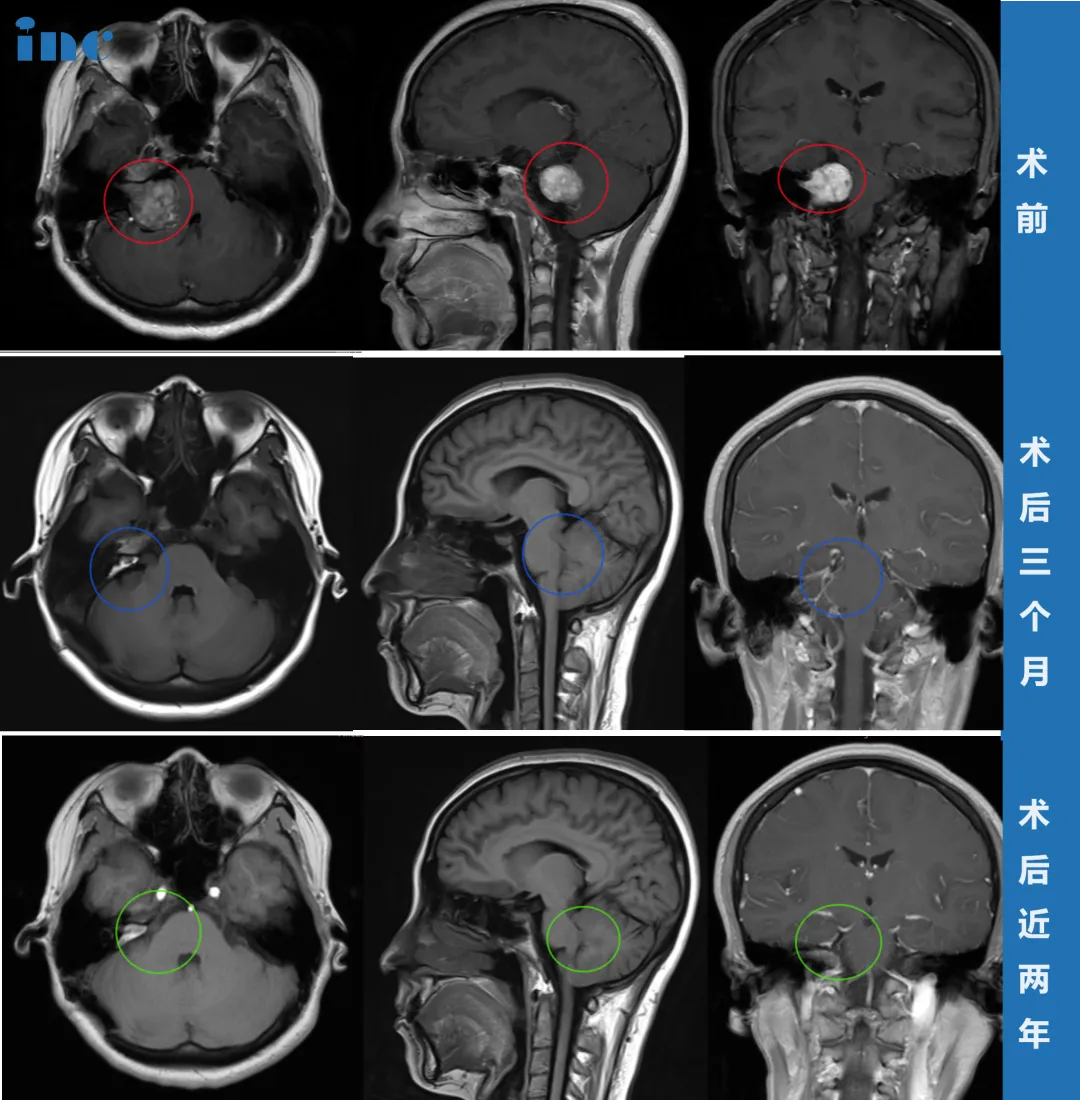

此次患者直接进行头颅核磁共振检查,结果确诊为右侧桥小脑角区(CPA区)前庭神经鞘瘤(听神经瘤),最大直径约35mm(含内听道部分),肿瘤压迫脑干、桥脑及右侧桥臂,第四脑室形态改变。回顾2019年CT影像,医生确认当时确实无法发现病变。

手术当日实施细节令患者倍感安心:未采用全头剃发,仅剔除手术区域头发;麻醉安全到位,全程生命体征监测;采用半坐位体位确保术中视野清晰。巴教授根据肿瘤位置和形态制定个体化手术入路,在神经电生理监测和MRI辅助下,于显微镜下精准完成肿瘤全切,全程保护神经功能及重要脑组织。

术后当日即拔除气管插管,患者完全自主呼吸。复查CT显示正常,无脑出血等并发症,随后转入普通病房康复。

出院时患者全身状态恢复良好:术前右侧面部麻木等症状明显改善。虽因手术水肿出现短暂面瘫,但经积极康复锻炼,术后2个月基本恢复,术后半年恢复良好,术后近2年无复发。